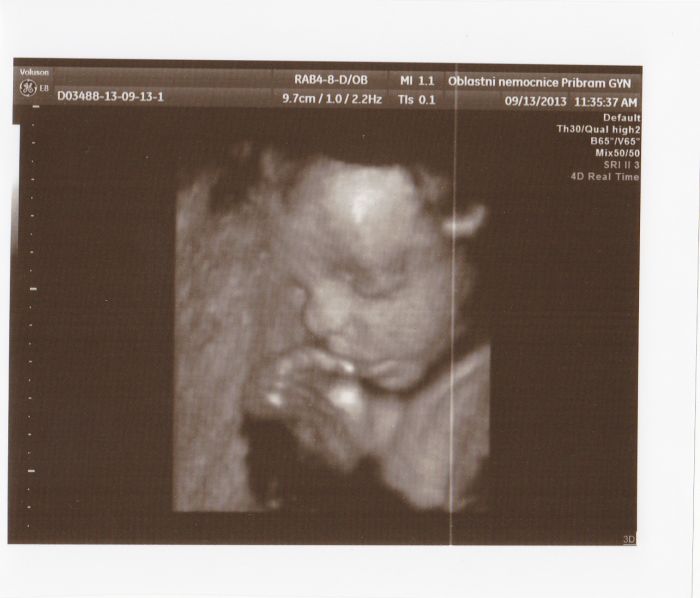

Autor: Martina 127 19.9.2013 v 15:21

taky posilam fotecky z 3D konecne jsem nasla kabel a povedlo se mi je dat do tabletu :-)